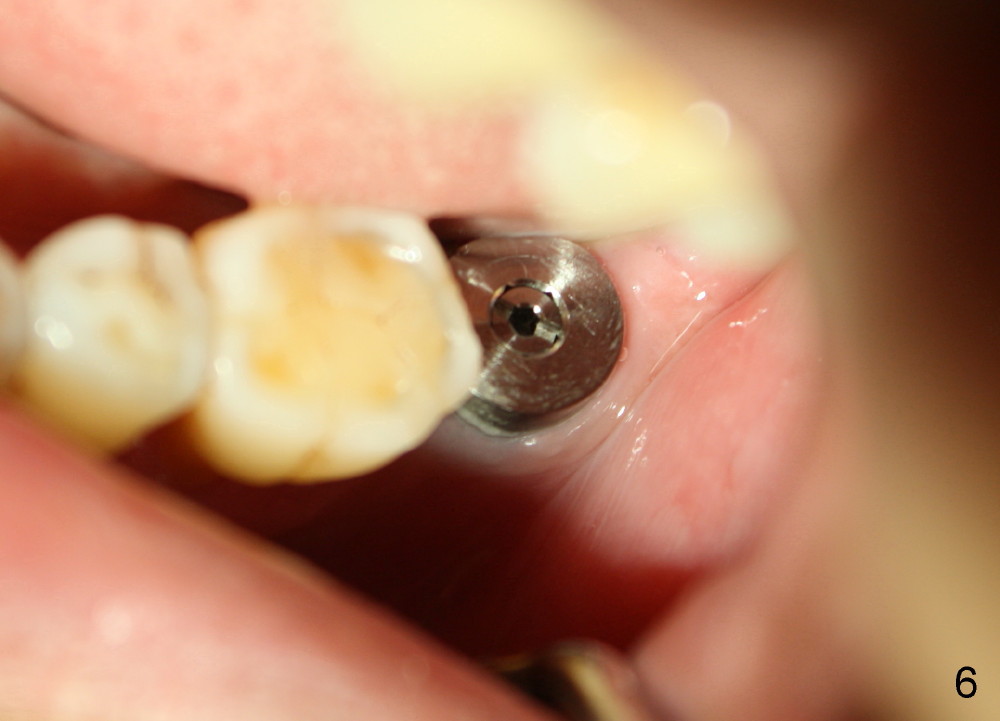

In contrast, the patient is asymptomatic after the 2nd placement.  The implant remains stable (Fig.6 (15 days postop); Fig.7 (4 months postop)).